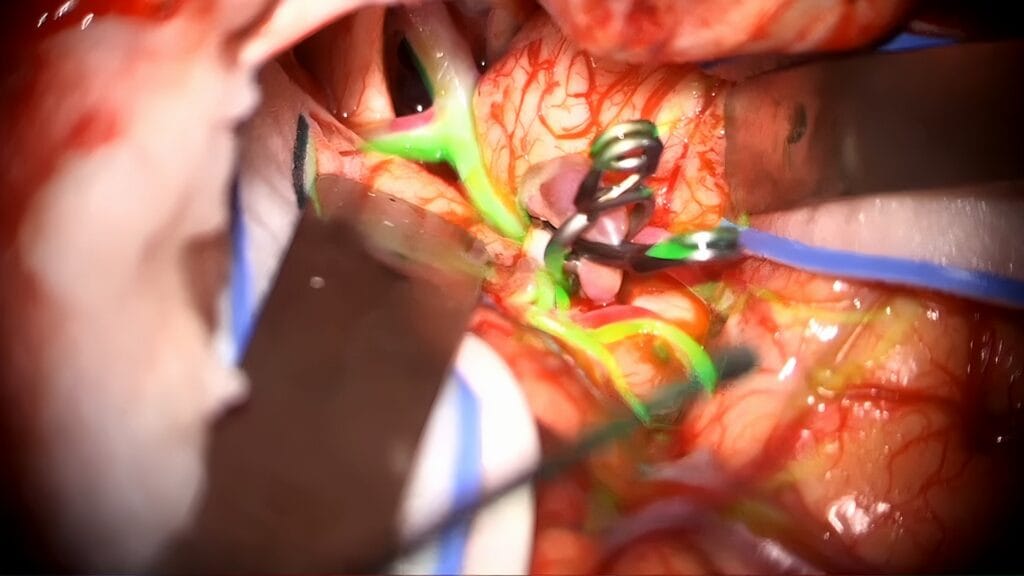

Clipaje transcavernoso de aneurisma de la ACS

Se presenta un caso de clipaje de un aneurisma de la arteria cerebelosa superior con un tratamiento previo con flow-diverter fallido.